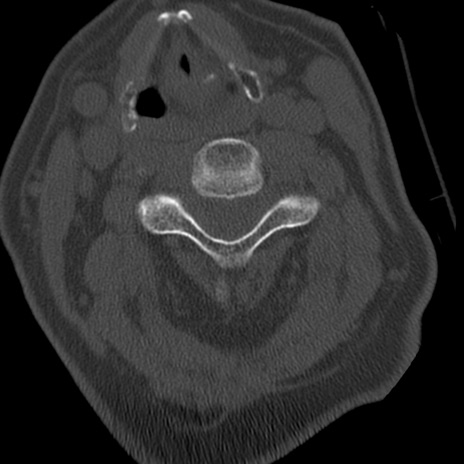

症例50 頚椎CT(横断像)

頚椎CT